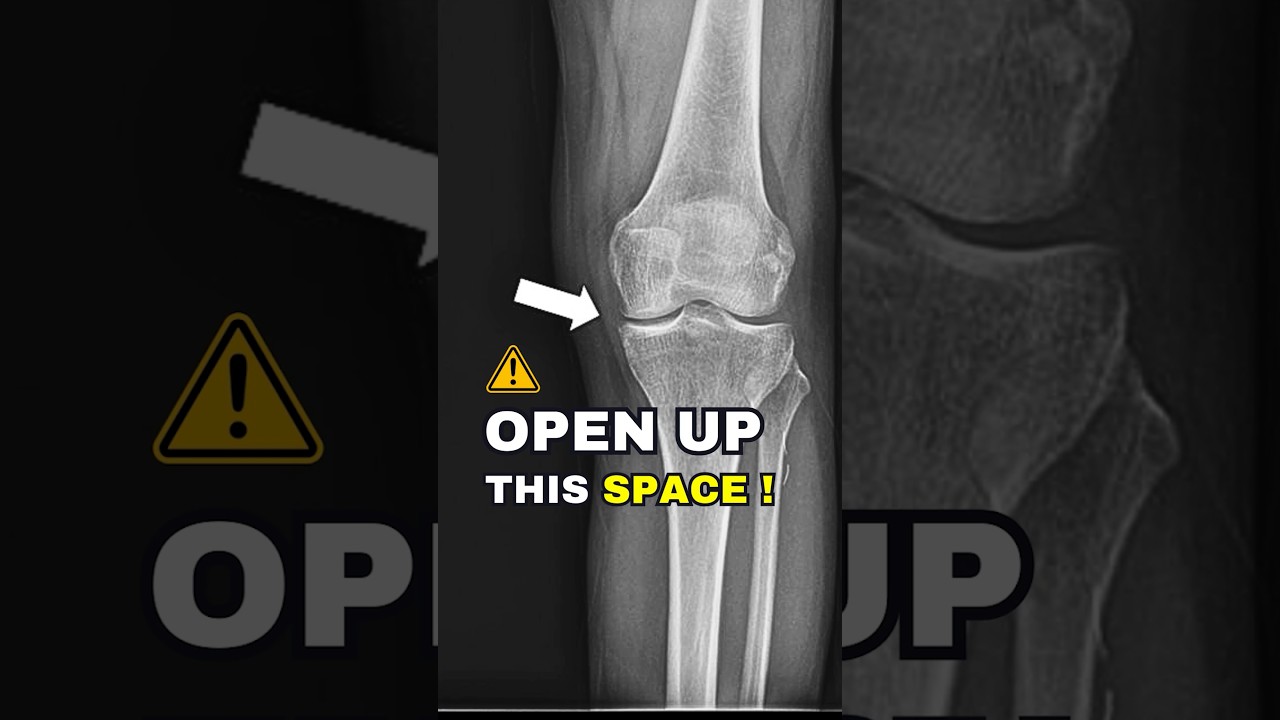

Did you know that strengthening muscles around the hip and ankle can significantly improve knee alignment in osteoarthritis? Weak hip internal rotators and ankle evertors can lead to faulty biomechanics, increasing stress on the knee joint.

By targeting these muscle groups, we can reduce pain and improve function. Let me show you how!